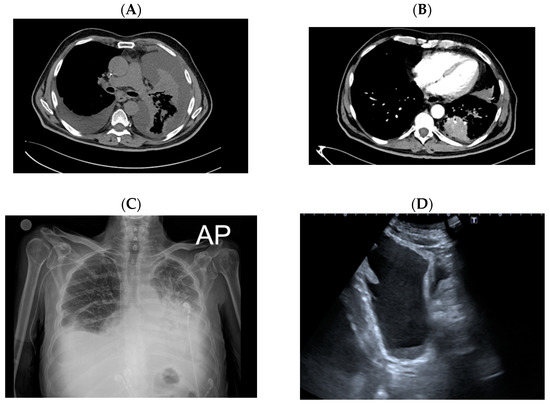

2. Case Report